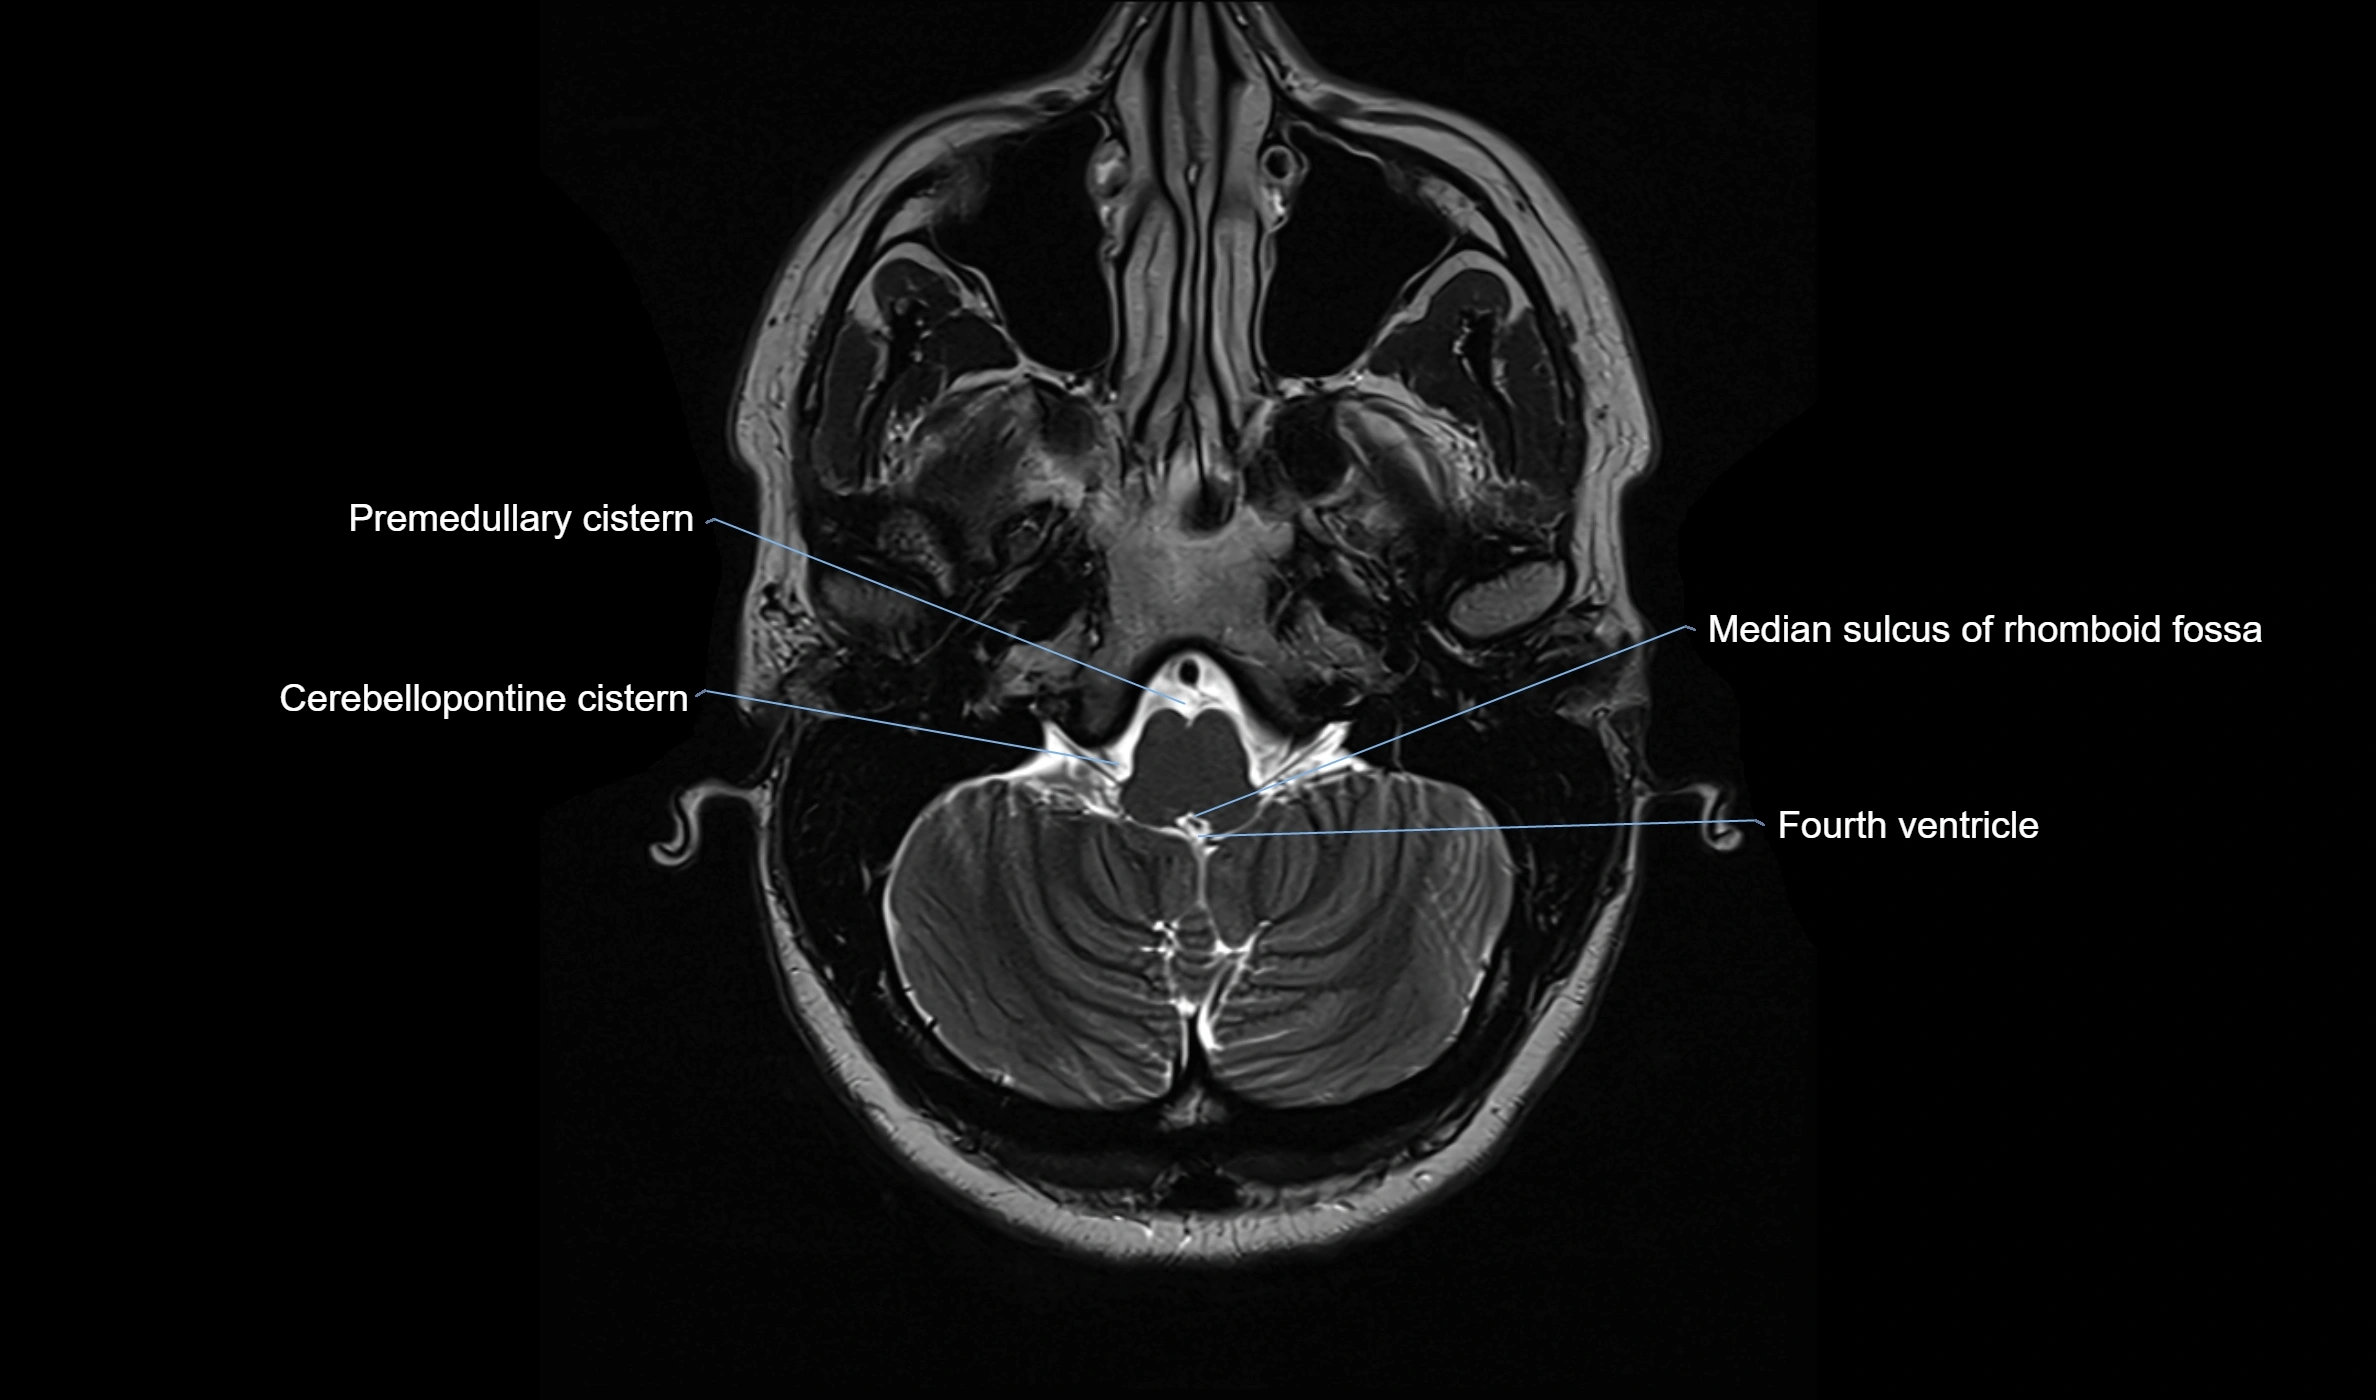

CT image

image